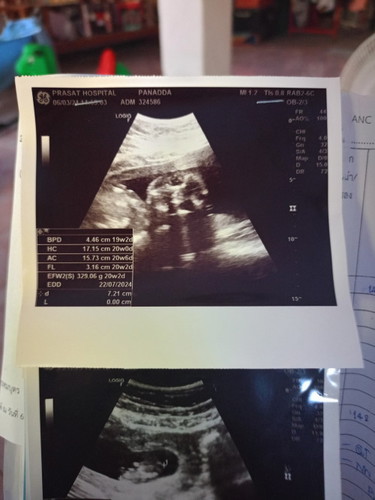

อยากสอบถามแม่ๆ ว่าลูกเพศอะไรค่ะ 20วีคแล้วค่ะ ลุ้นมาก ช่วยดูหน่อยค่ะน้องเพศไหน 😁🌼